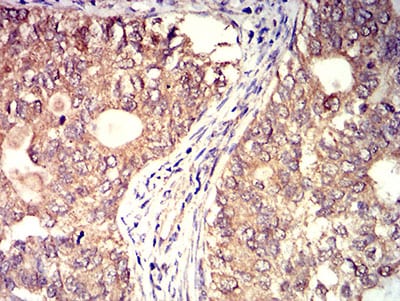

Immunohistochemical analysis of paraffin-embedded human cervical cancer tissues using BTN2A2 mouse mAb with DAB staining.